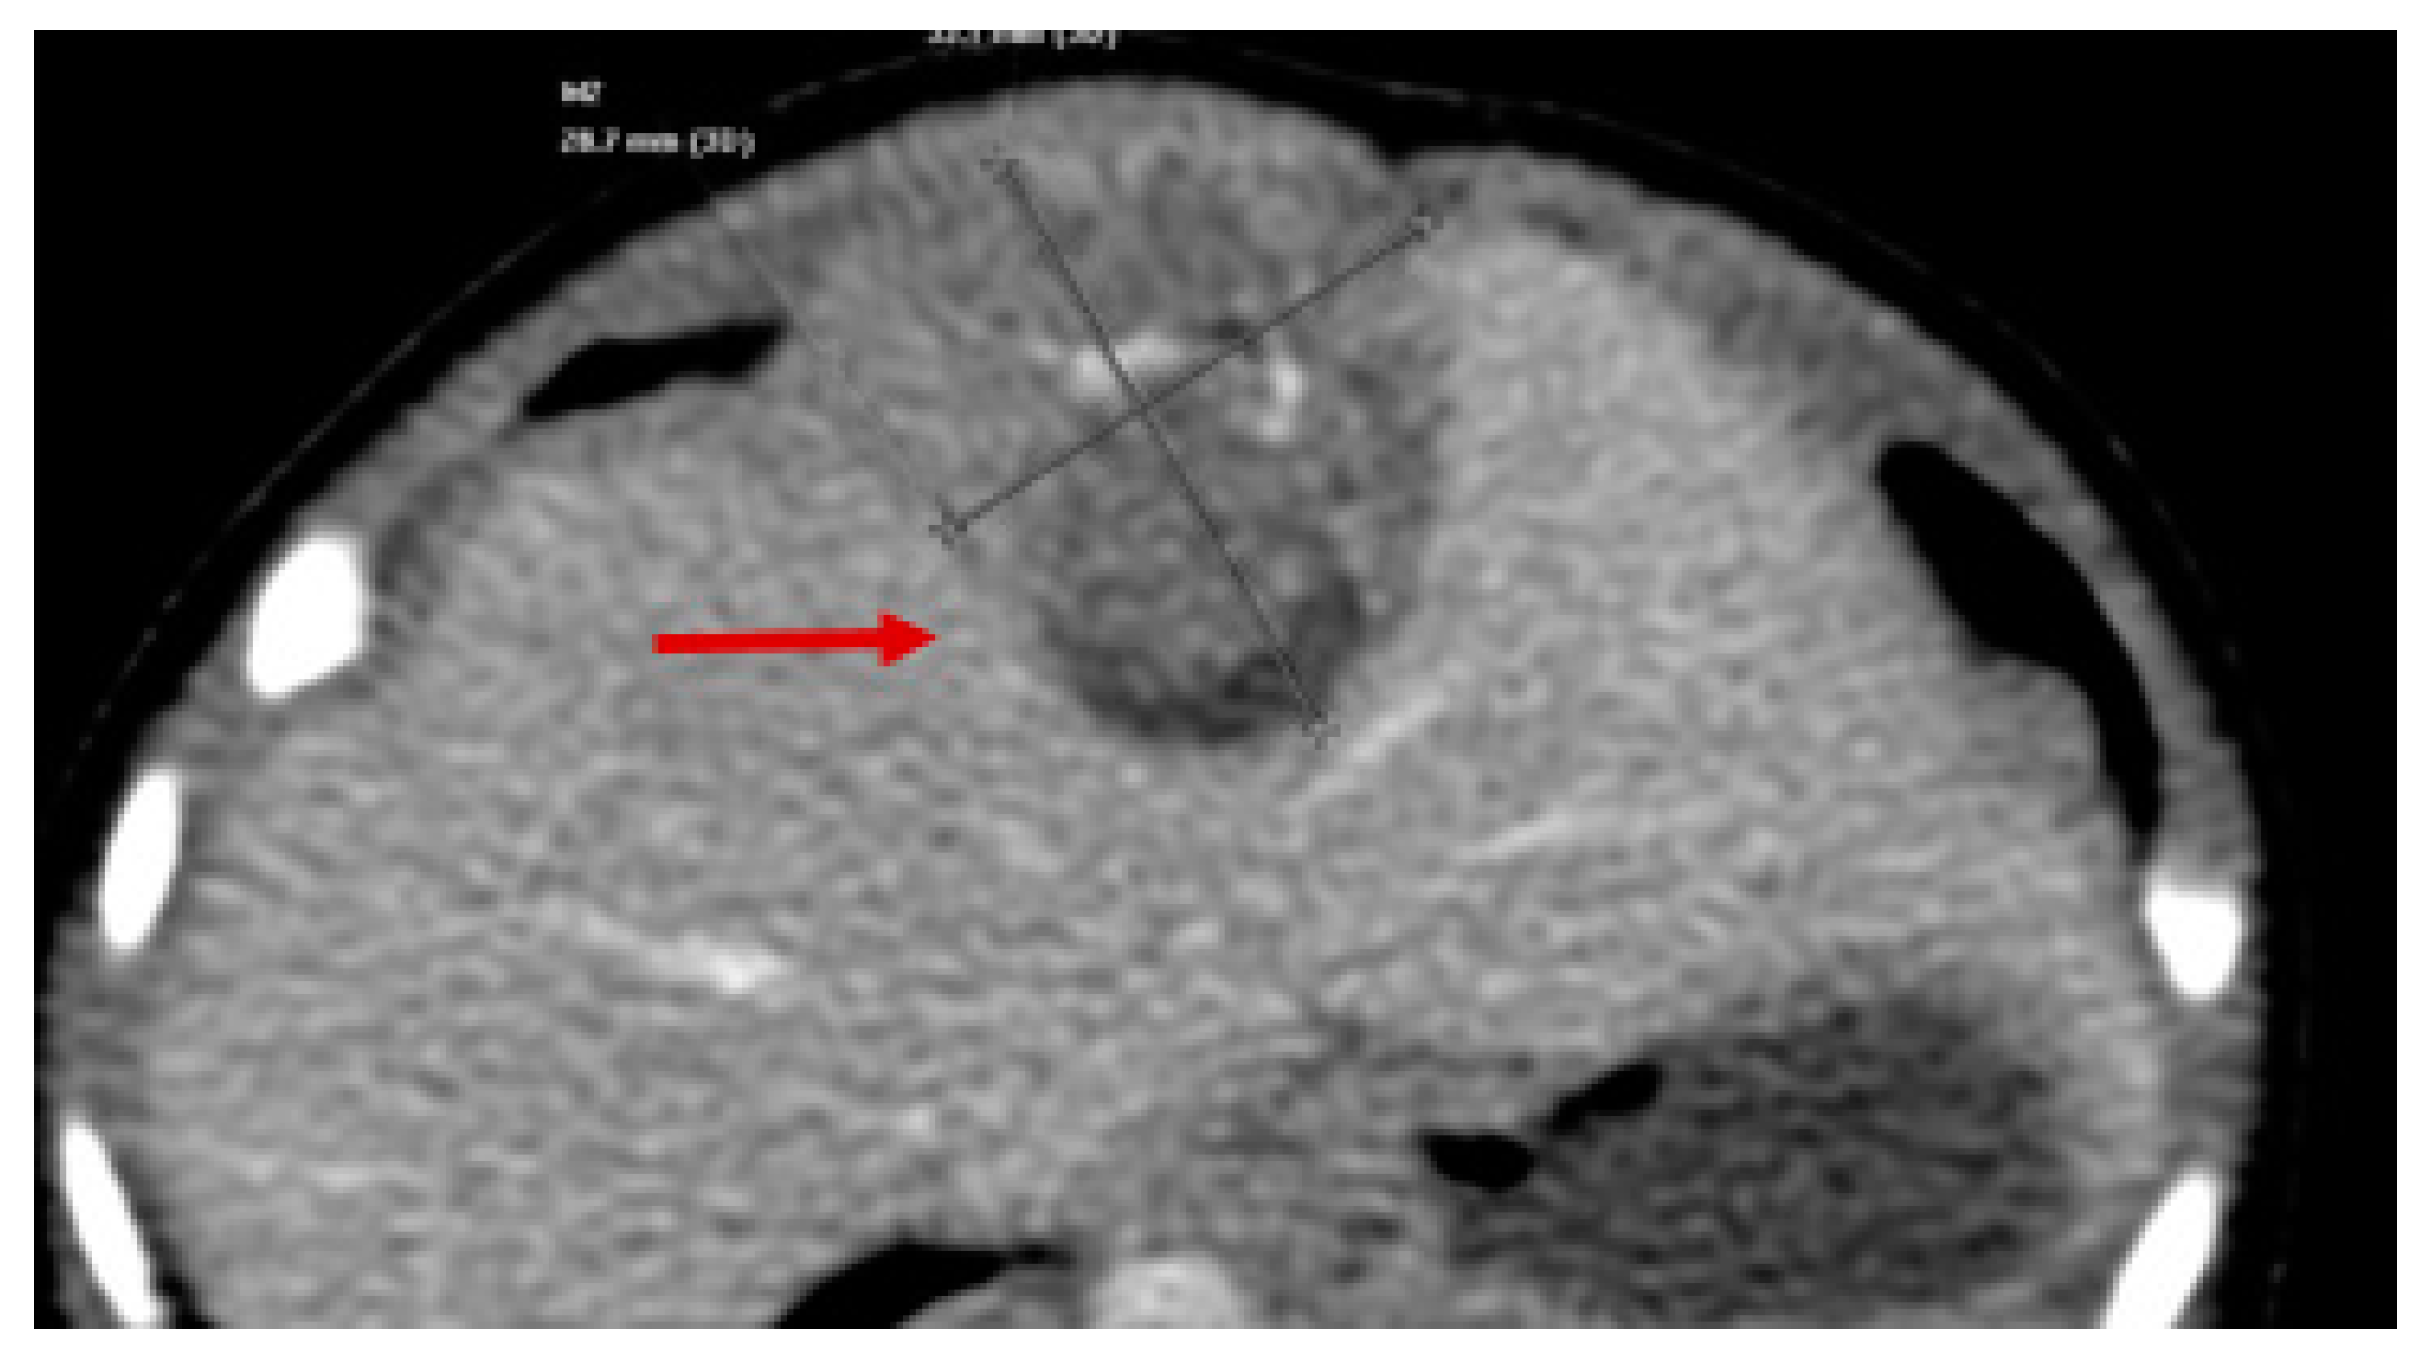

3. Presentation

4. Assessment

14. Assessment